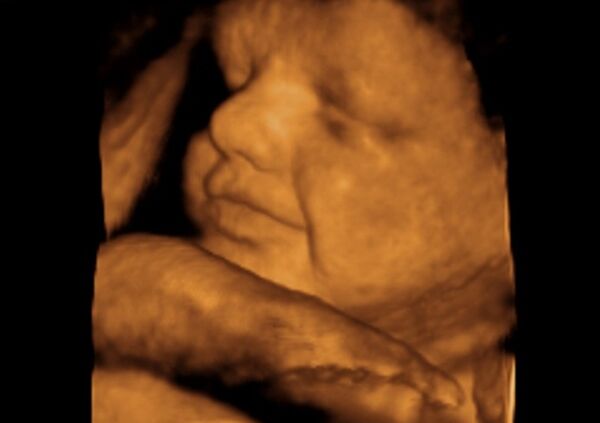

Bebekler anne karnında ne yapar?